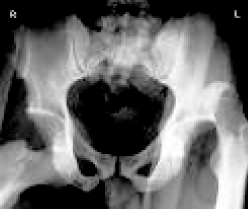

患者X线检查

患者,女性,32岁,已婚,农民,因车祸后右髋部疼痛不能活动2小时入院。患者于2小时前因乘车时汽车紧急刹车,右膝部撞击前面座位,立即感到右髋部疼痛、不能站立及活动,被送来本院。入科时查体:患者神志清醒,痛苦面容,营养良好,微胖体型,全身皮肤黏膜无黄染,右髋部肿胀、压痛,可触及脱出股骨头,右下肢呈屈曲内收内旋畸形,右髋关节呈弹性固定,右下肢末梢血运感觉可。辅助检查:X线检查示右髋关节后脱位。诊断为右髋关节后脱位。